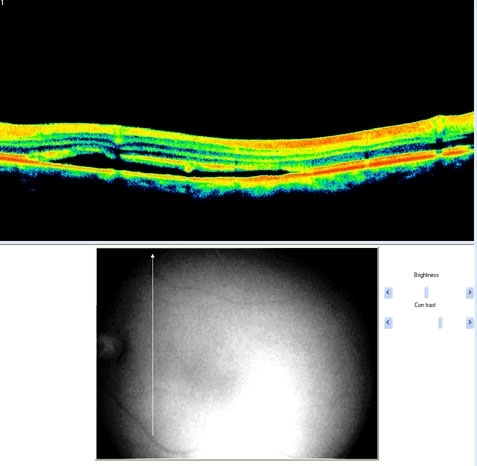

Fundus Appearance - Clinically, there is a localized retinal elevation (detachment). There may also be a detachment of the outermost layer of the retina called retinal pigment epithelium (RPE). There may be some small yellow spots in the area of detachment. There may be other areas with changes in pigmentation which are believed to correspond to previous CSR episodes

csr1 csr3

csr2